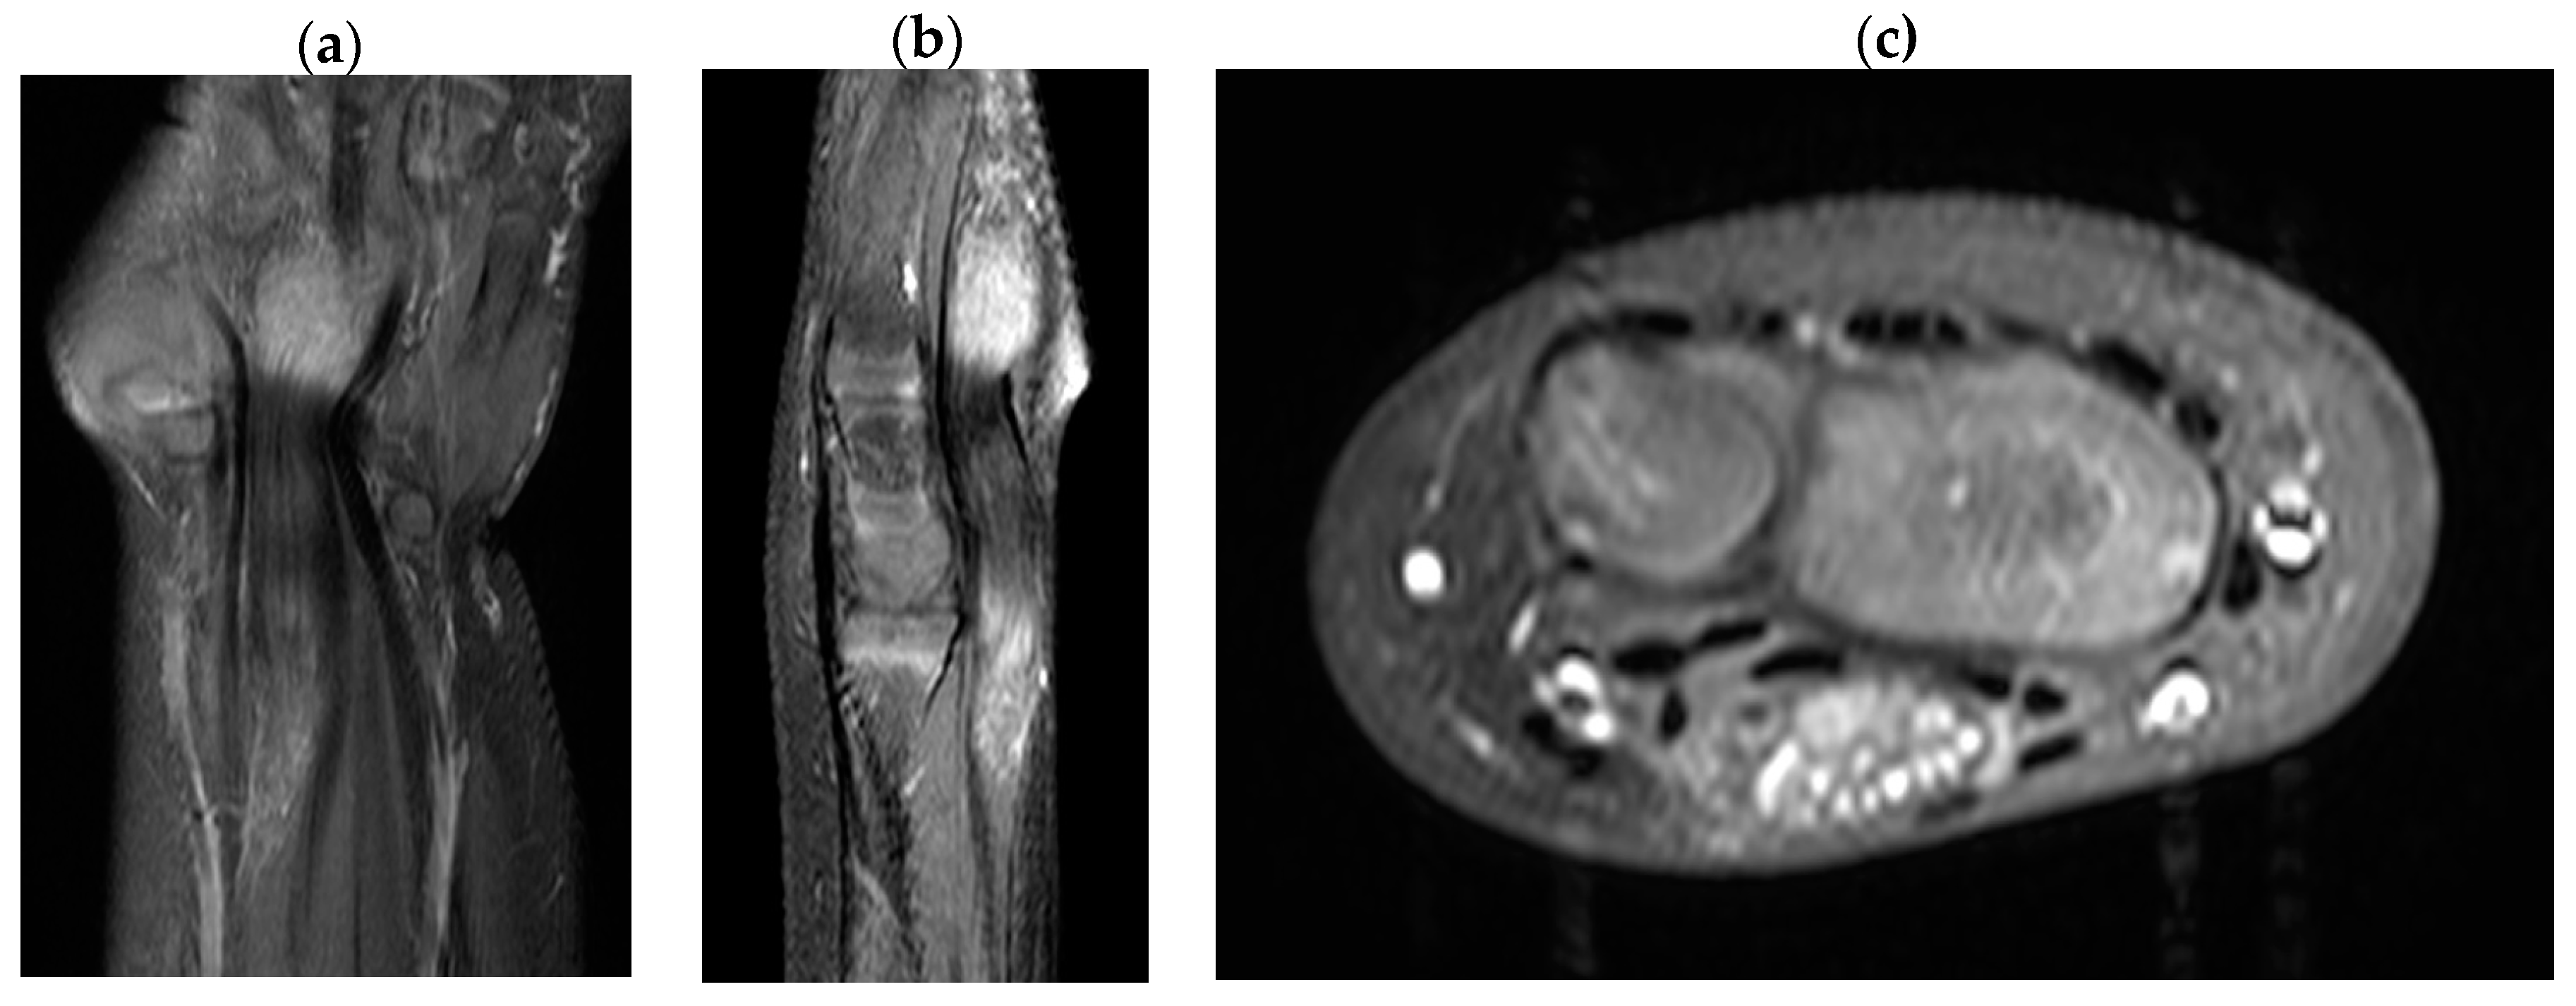

Ultrasonographic examination on the first visit to the clinic showed severely edematous and hypertrophied median nerve from the left wrist level down to the palm with low-echogenic intraneural multiple fascicles (Figure 2). In addition, subsequent enhanced magnetic resonance imaging of the left wrist indicated fusiform enlargement the median nerve from the left forearm distal 1/3 area down to the left hand metacarpal area along with characteristic findings of longitudinally-oriented cable-like appearances of the tumor in addition to its invasion into flexor retinaculum Figure 3).

In the diagnosis of LFH, MRI plays a critical role by offering pathognomic radiologic features, low-intensity serpentine nerve fibers embedded in abundant high-intensity adipose and fibrous tissues, also known as “cable-like appearances”.[9] In addition, ultrasonography also serves an essential tool for initial diagnosis and postoperative non-invasive radiologic follow-ups. Ultrasound imaging of LFH is characteristic of the enlarged cross-section of the affected nerve with hypoechoic fascicles embedded in the hyperechoic fibrous and adipose tissues, and recent ultrasonography has shown to provide as equivalent diagnostic evidence as MRIs.[10] While MRIs are beneficial in assessing the extent of the lesion in the initial diagnosis, ultrasonography serves a critical role in serial postoperative follow-ups, as seen in the current case description. However, biopsy and histologic examinations are the only definitive measures for the diagnosis of LFH, which are characteristic of intertwining collagen, fibroblasts, and adipose cells separating nerve fascicles and infiltrating the space between the epineurium and perineurium without inflammation or myelin degeneration.[2]

Figure 2. Wrist ultrasonography shows thickened and hypoechoic intraneural fascicles (white crosses).

Figure 3. T1-Magnetic resonance imaging of the lipofibromatous harmatoma in the median nerve. (a) coronal view (b) sagittal view (c) axial view.